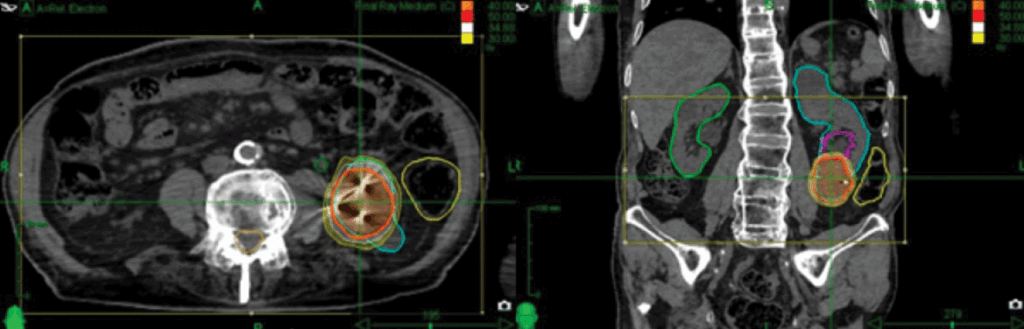

Organs at RiskKidneys, bowel, spinal cord, liver (figure 1)

Figure 1: Left renal volume delineation from the treatment CT scan in the axial and coronal planes.